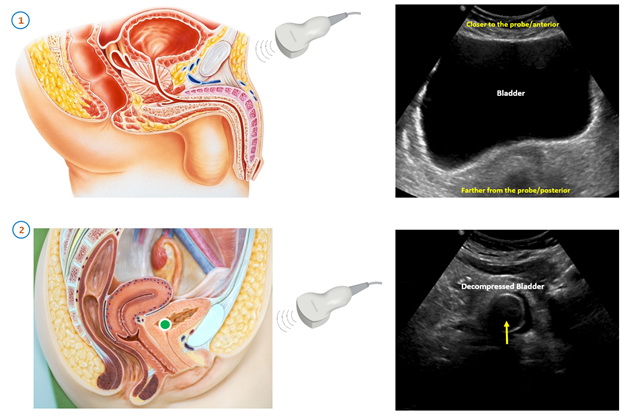

Трансабдоминальное УЗИ проводится лежа. Врач перемещает ультразвуковой датчик по нижней части живота, изменяя углы и направление, чтобы получить изображения мочевого пузыря с разных ракурсов. Во время процедуры врач может попросить пациента немного задержать дыхание или напрячь мышцы брюшного пресса, чтобы улучшить визуализацию.

Исследование проводится при наполненном мочевом пузыре. Заблаговременно до начала процедуры выпивается около 1 литра воды. Не стоит стремиться к при слишком переполненному мочевому пузырю, так как результаты могут быть менее точными.